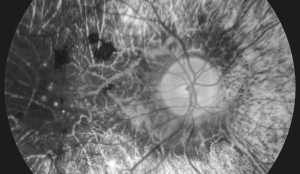

• Non-Proliferative Diabetic Retinopathy (NPDR)

Non-Proliferative Diabetic Retinopathy (NPDR)

This form accounts for about 80% of diabetic retinopathy cases. Blood leaks from the retinal vessels, causing retinal hemorrhages and macular edema. If left untreated, it can progress to proliferative diabetic retinopathy.